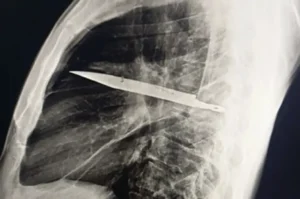

Doctors who examined him during this recent visit ordered an X-ray, which revealed a “retained metallic object” inside his chest. Further imaging confirmed the shocking finding: a knife blade had penetrated through his scapula (shoulder bone) and remained lodged deep within the chest cavity. Around the blade, a significant build-up of pus and necrotic tissue had formed, a sign that his body was beginning to respond to the foreign object after years of relative silence, according to PEOPLE.

A diagram showing the knife’s location in the chest with associated healed fractures. Credit: National Library of Medicine.